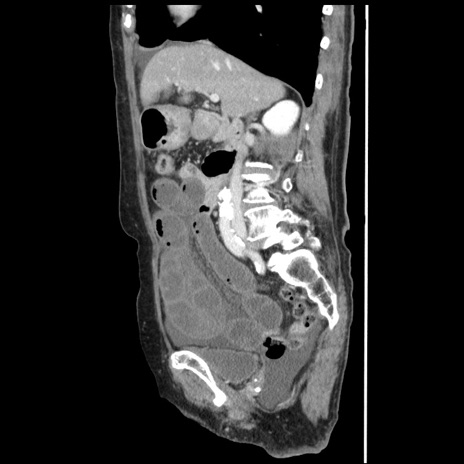

冠状断像

【症例】80歳代女性

【主訴】腹痛

【現病歴】8時間前から腹痛あり来院。

【既往歴】糖尿病、脂質異常症、子宮体癌にて子宮全摘術

【身体所見】意識清明・会話良好だが腹痛で苦悶様、全腹部にわたって反跳痛と圧痛あり

【データ】WBC 13600、CRP 0.14、LDH 224、CK 90